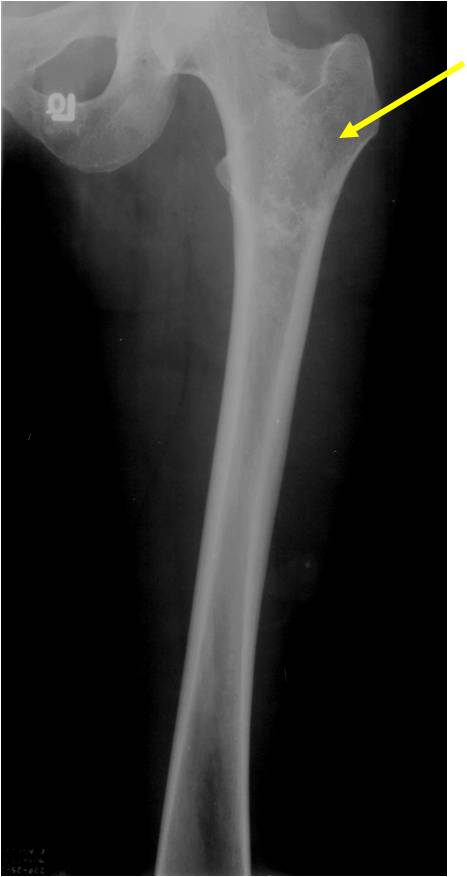

- Proximal Humerus, Femur most common long bones

- Localized, radiolucent defect usually with punctate calcifications

- Calcifications are stippled, punctate, popcorn like calcifications and “Ring and Arc” calcifications

- Most commonly found in metaphysis

- Geographic lytic lesion

- Central often metaphyseal in long bones

- Expansile remodeling with thinned cortex

- Chondroid matrix with calcifications in majority of tumors

- Approximately 20% have limited or no calcifications